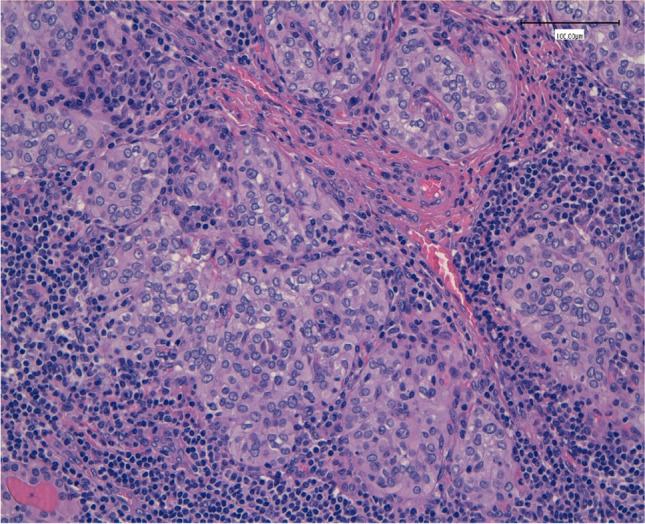

Our study attempts to analyse the possible significant relationship between these two entities and the impact of HT in the prognosis of PTC. The incidence of HT in our large case series of PTC patients reached 41.4%, finding 180 patients (out of 435) with a histological diagnosis of HT associated with the presence of a PTC (Fig. 2).

Fig. 2.

The lymphoid infiltrates penetrating among the papillary carcinoma aggregates